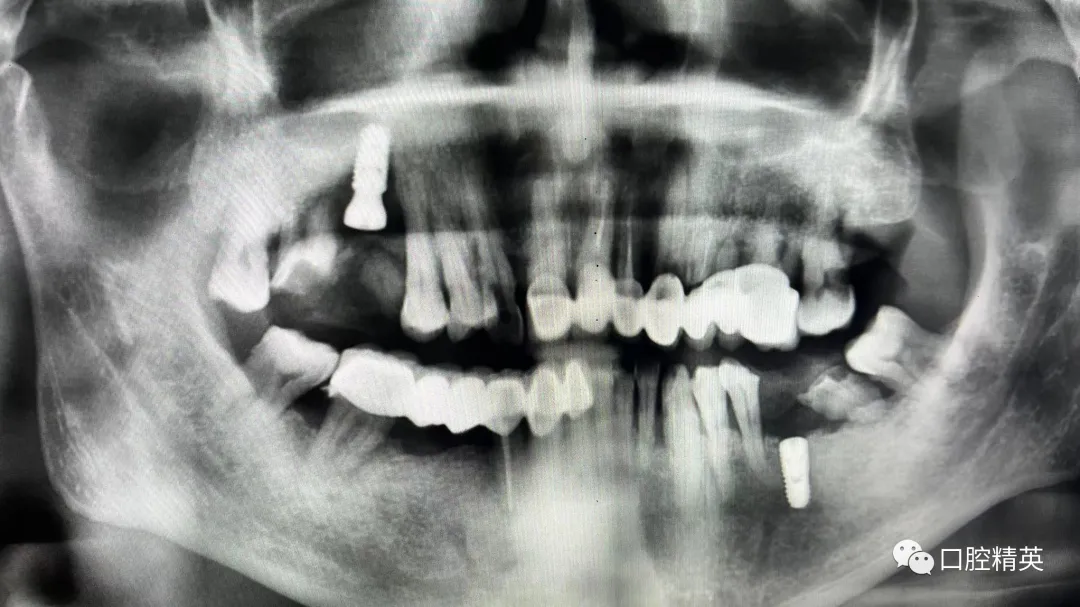

7、种植影像学分析;可以获得骨高度 ,骨宽度信息 ,甚至可以模拟种植体植入位点

七、种植初级往期期部分培训影像